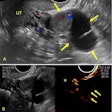

Why don't more women get UFE?

One of the first studies to come out of SIR 2017 is research on the utilization of uterine fibroid embolization (UFE) as an alternative to hysterectomy for women with painful fibroids. Despite the advantages of UFE in terms of cost and noninvasiveness, use of the technique pales in comparison to open surgery, researchers found. Get the details by clicking here.